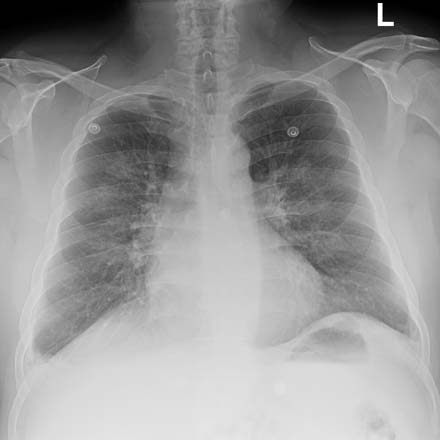

Imagen que muestra insuficiencia cardíaca.

Nota: Las imágenes se muestra para fines ilustrativos. No trate de sacar conclusiones comparando esta imagen con otras en el sitio. Solamente los radiólogos calificados deben interpretar las imágenes.